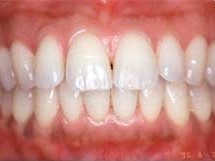

歯周炎はお口の中の細菌が引き起こす口腔内二大疾患の一つです

歯周炎はお口の中の細菌が引き起こす口腔内二大疾患の一つです。

進行すると歯を支える歯槽骨が吸収し、歯がぐらつく状態へと進みます。

さらに重症化すると急性炎症や膿瘍を生じ、歯を失う可能性もあるため注意が必要です。

歯ぐきの赤みや腫れ、ブラッシング時の出血がみられる場合は、痛みがなくても診査を受けることが勧められています。

近年では、進行した歯周炎であっても快復を目指す治療が可能になってきました。

糖尿病との相互関係も指摘されており、全身的な視点を含めた口腔ケアが重要とされています。

歯周病治療では、自己管理としての正しいブラッシング、高い水準の治療、そして治療後のメインテナンスという三つの柱が大切です。

患者様による日々のケアと、歯科医師・歯科衛生士による専門的処置が連携してこそ、良好な結果につながります。

治療は応急処置から始まり、精密検査、カウンセリングを経て初期治療へと進みます。

歯石除去やブラッシング改善を基本とし、必要に応じて歯周外科手術や再生療法を行います。

修復治療後は1~6か月ごとの定期検診を通じて状態を維持します。

歯石はブラッシングでは除去できないため、スケーリング・ルートプレーニングなど専門的処置が必要です。

レーザーは補助的に応用されることがありますが、それだけで完結する治療ではありません。